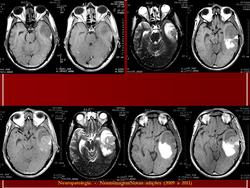

ГМ. Примитивная нейроэктодермальная опухоль (ПНЭО). +

Примитивная нейроэктодермальная опухоль (ПНЭО)